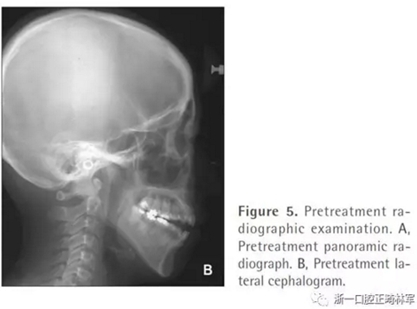

全景片顯示四顆智齒都存在,上頜切牙有牙根吸收,并且在雙側(cè)髁突都有相當(dāng)大的吸收(Figures 1B and 5A)。頭測分析顯示:ANB angle, 4.5°; FMA, 46.7°; U1-SN, 95.8°; L1-MP, 83.7°(Table 1, Figure 5B)。

基于上述檢查結(jié)果,患者被診斷為雙側(cè)髁突形態(tài)改變引起的開合畸形。